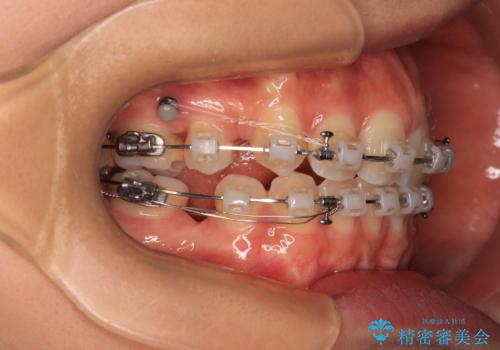

- 矯正装置

- クリアブラケット

口元の突出感が認められ、更には左右で異なる咬合状態であったため、下顎右側は第二小臼歯を、左側は第一小臼歯を抜去することでバランスを取るような治療計画としました。

また上顎前歯は大臼歯に補綴治療が必要であったため、矯正治療後にオールセラミッククラウンによる補綴治療を行うこととしました。